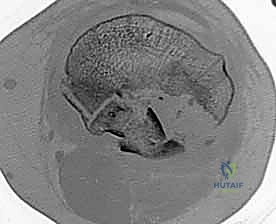

Image

FIG 1 • The Mayo classification of olecranon fractures accounts for the factors that will influence treatment decisions: displacement, comminution, and dislocation or subluxation of the articulations.